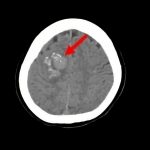

病名

断層撮影